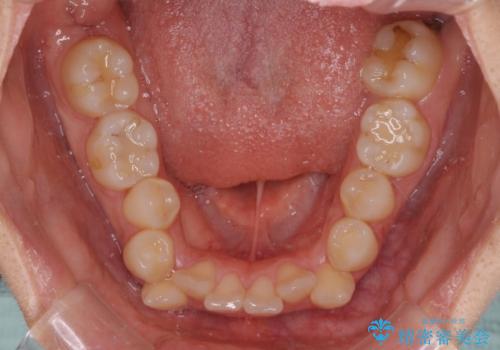

- 咬み合わせと、前歯のデコボコや八重歯、飛び出した口元を気にして来院された患者様です。

上顎は歯列不正が強く、右側臼歯部の咬み合わせは歯1本分ずれている状態でした。

補助装置を用いて奥歯の咬み合わせを改善しながら歯列を後方に移動させ、上下左右第一小臼歯を4本抜歯することで八重歯や口元の突出感を改善することとしました。